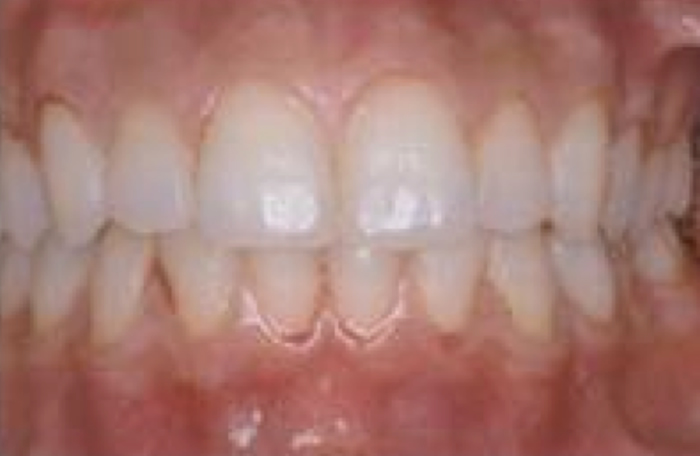

軽度歯肉炎の症状

軽度の出血が認められます。

良好な口腔衛生とプラーク、歯石の除去を適切にすることで、歯肉炎は元の健康な状態に戻ります。